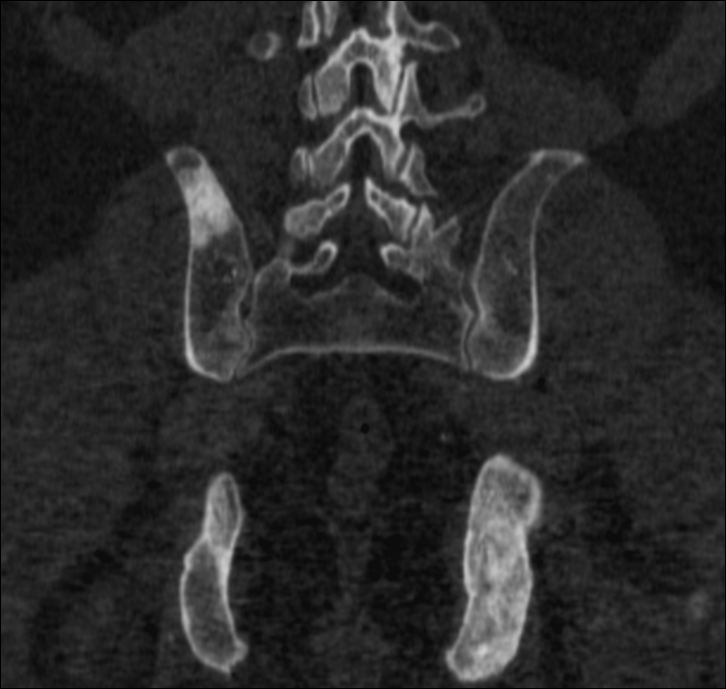

More complex anatomic structures (spine, the base of the skull, facial and hip bones) can be imaged more confidently with SPECT scans. On one hand, they provide a more accurate spatial localization and on the other, with their superior contrast resolution, they are able to differentiate lesions even if planar exams are negative or uncertain. SPECT-CT can characterize the CT morphology of the lesions with pathologic uptake. Thus, it is capable to provide a definitive diagnosis. (Figure 4.)

Image

a

b

c

d

e

4. Bone scintigraphy, prostate cancer. The image set shows the characterization of multiplex increased activity uptake. Posterior whole body scan (a). SPECT-CT coronal fusion images (b,d), CT examination (c,e). Sclerotic lesions in the pelvic bones are suggestive of osteoplastic metastases (b,c), small joint arthrosis at LIII-IV segments, more expressed on the left side (b,c), spondylosis on the right side at LIV-V segments (d,e). (The increased activity spot on the whole body scan, at the left cubital region, is correspondent to the paravasation of the iv. radiopharmaceutical.)